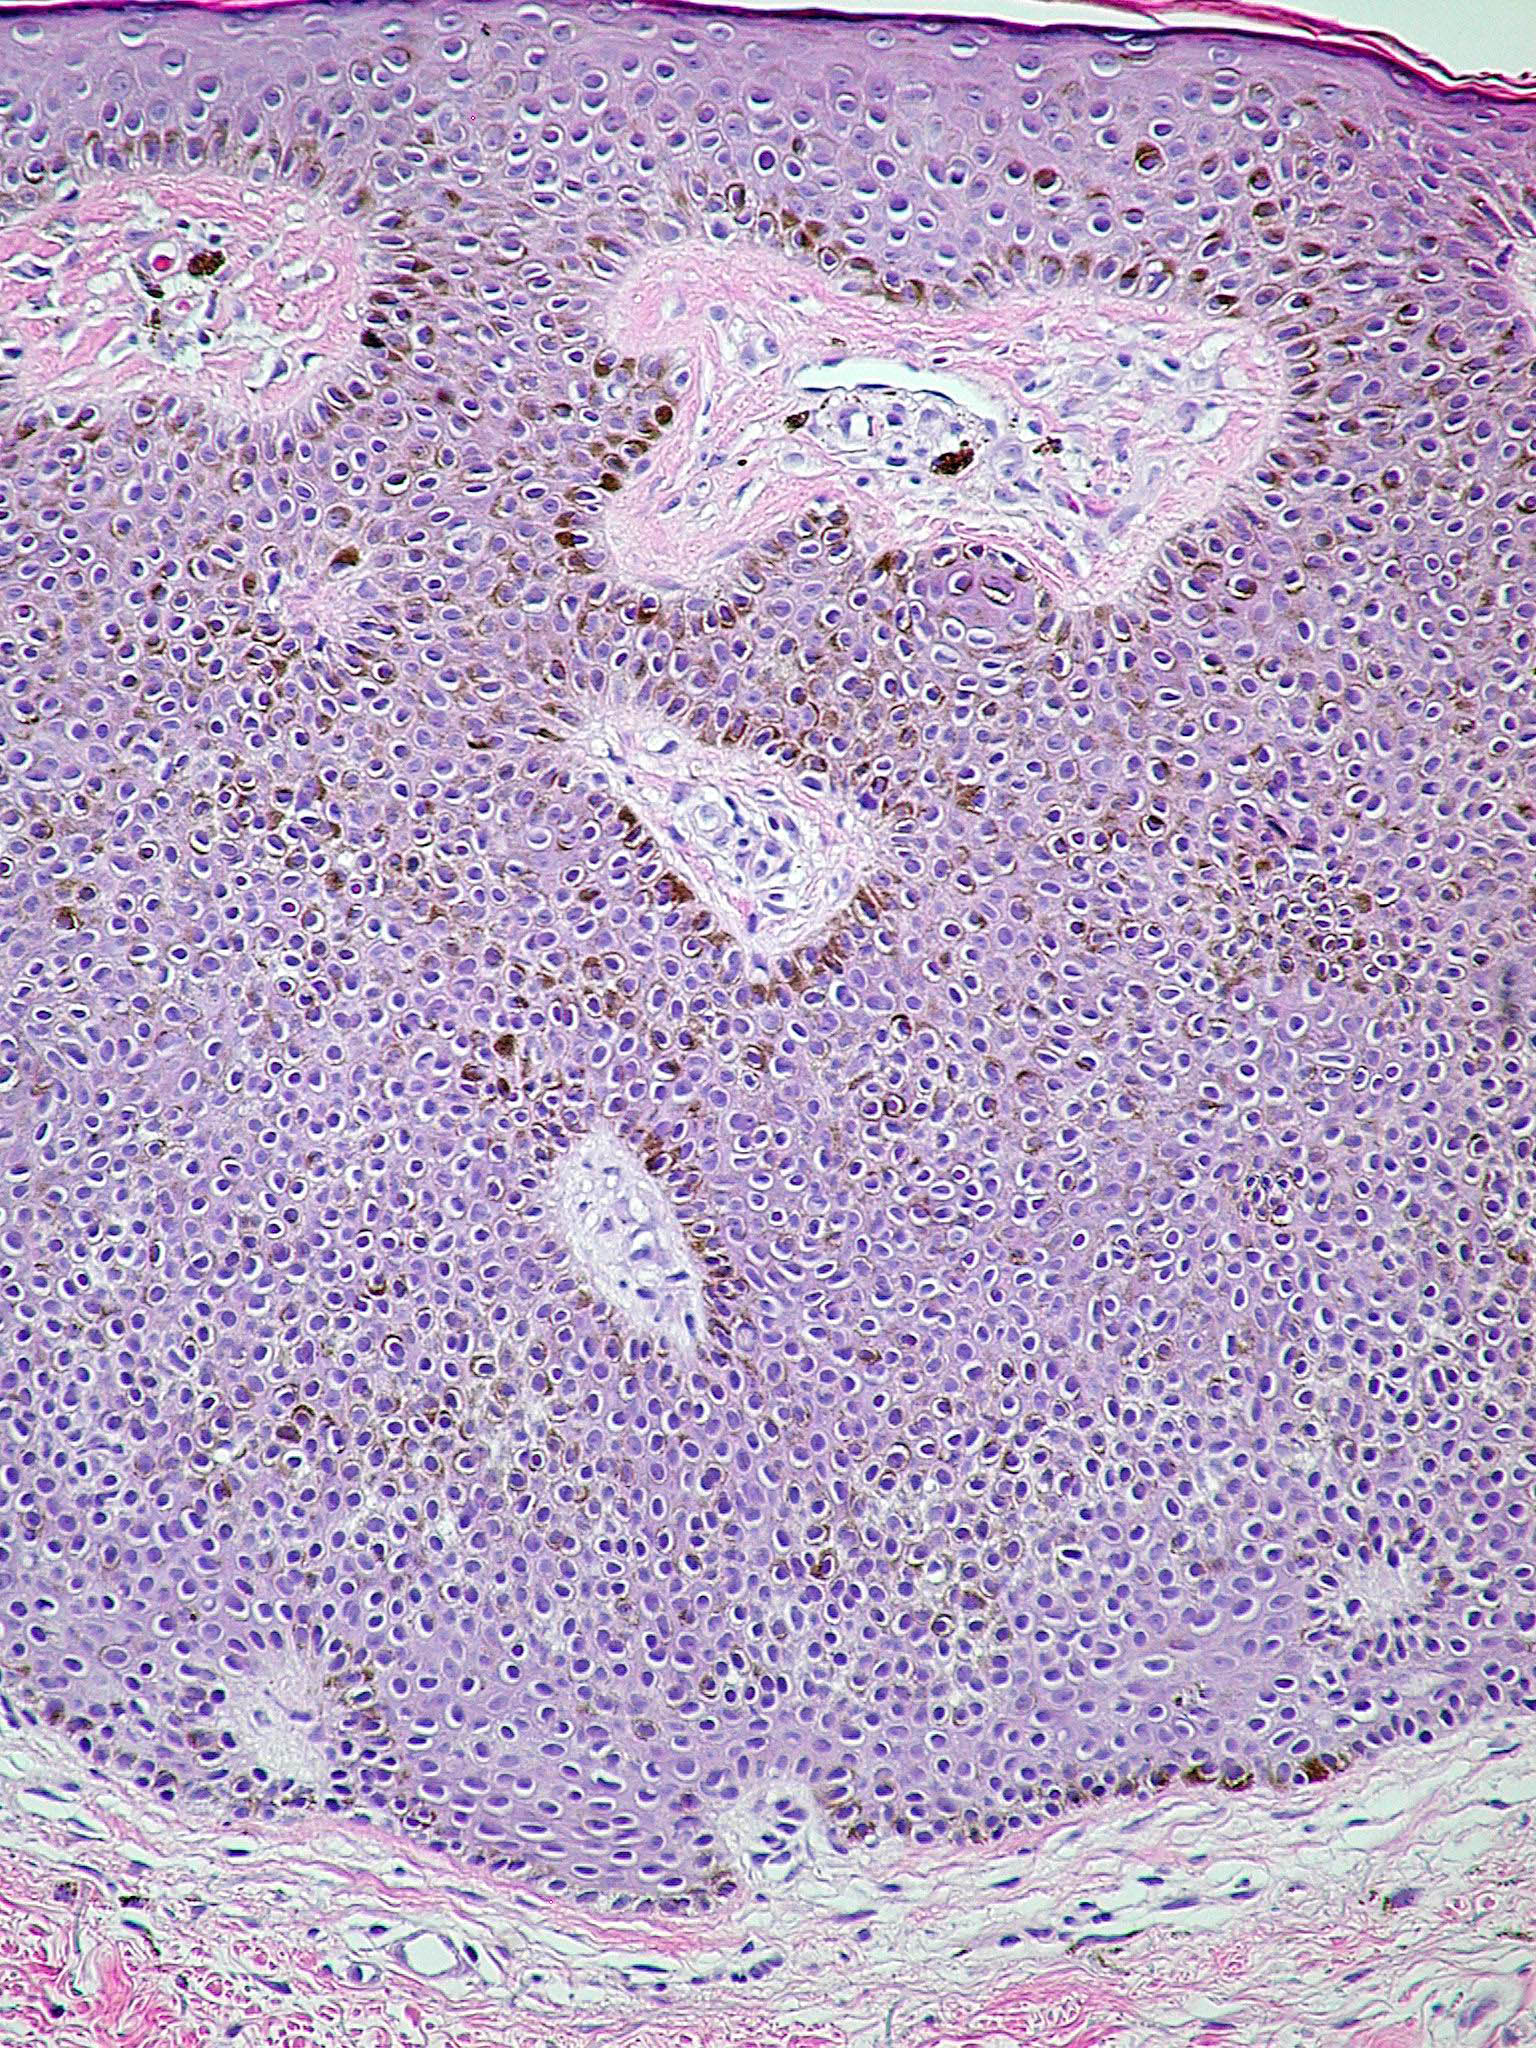

Seborrheic keratoses = التقران الدهني